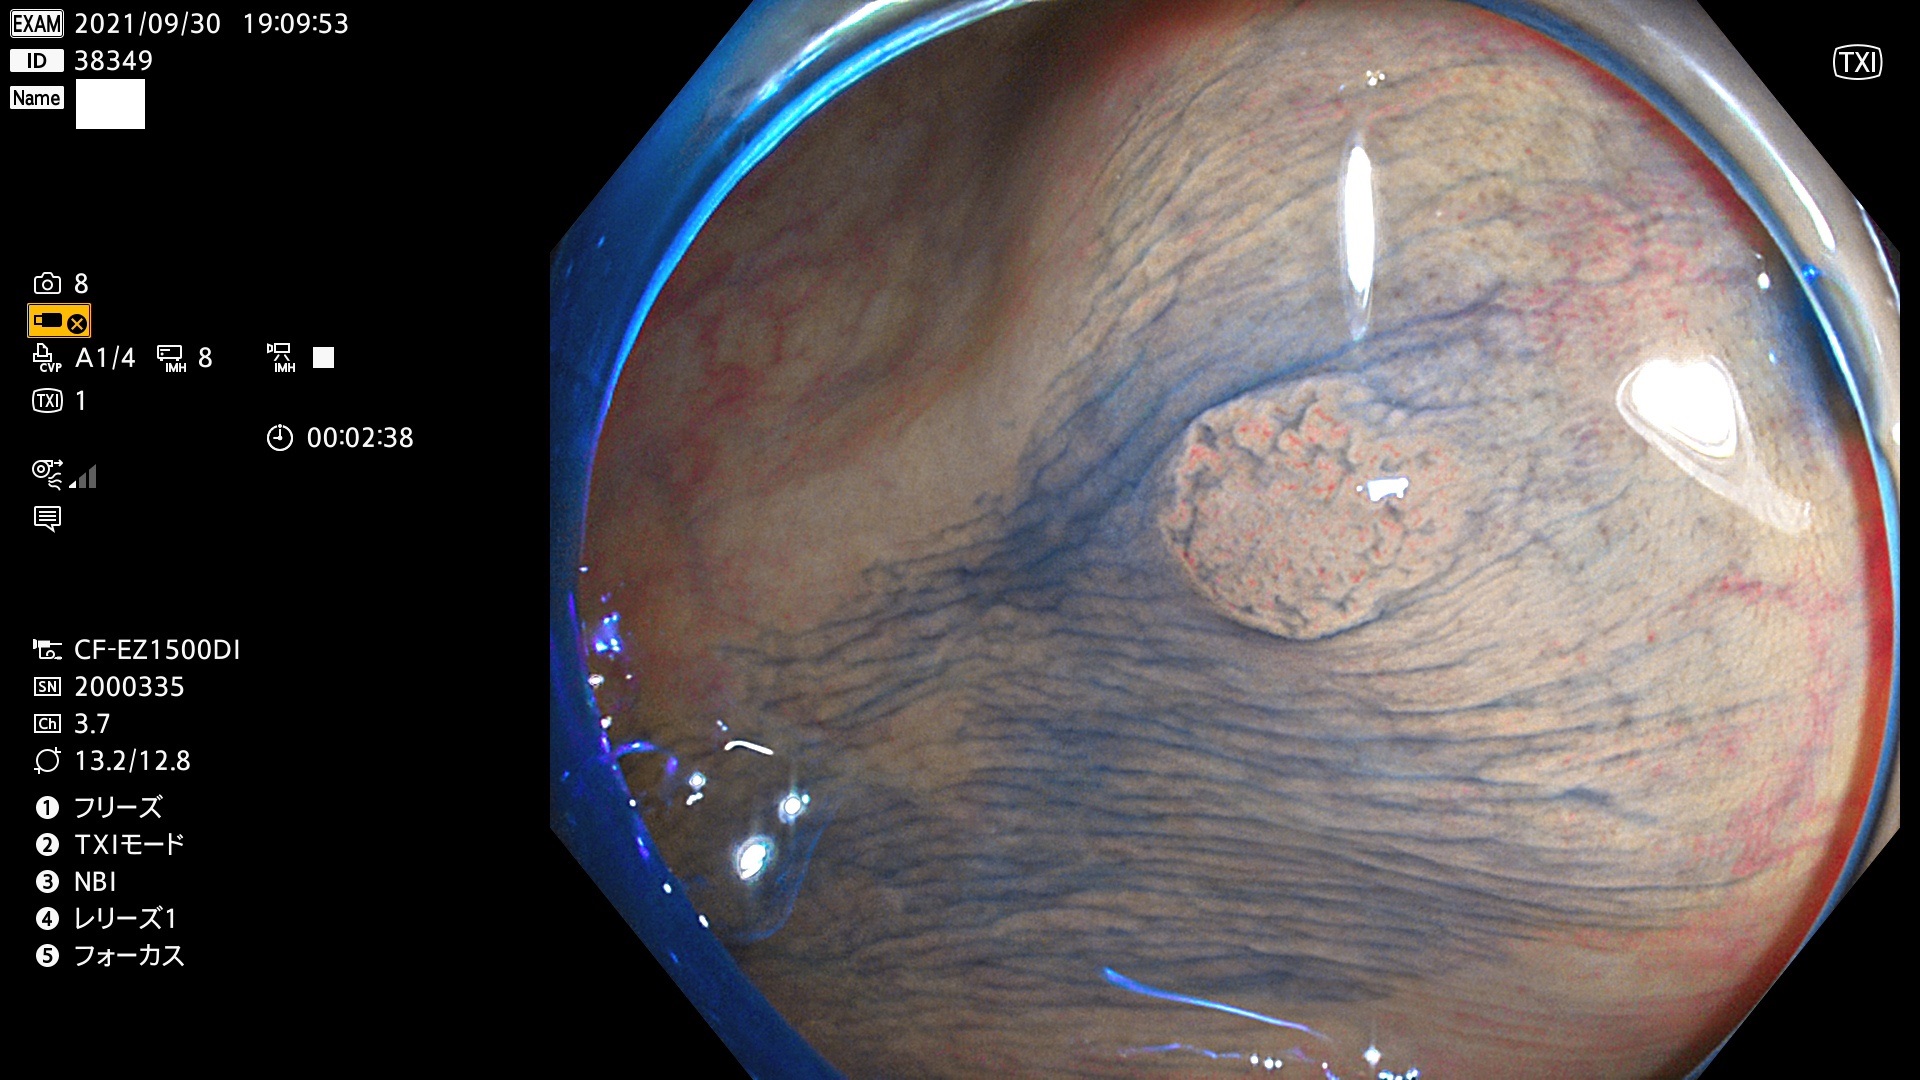

38300 38301 38302 38303 38304 38306 38307 38308 38309 38310 38311 38312 38313 38314 38315 38316 38317 38319 38321 38322 38323 38324 38325 38327 38331 38332 38333 38334 38337 38338 38339 38340 38341 38343 38346 38348 38349 38350 38351 38352 38353 38354 38355 38358 38359 38360 38361 38362 38363 38365 38366(SSAP) 38368 38369 38370 38371(SSAP) 38372 38374 38375 38376 38377 38378 38380 38381 38382 38383 38384 38385 38386 38388 38389 38391(SSAP) 38395 38397 38399

発見困難で危険性の高い平坦型病変(上記100名より抽出)